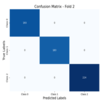

is a disruptive MedTech startup specialising in ARTIFICIAL INTELLIGENCE (AI) devoted entirely to the field of aiding the diagnosis

and early detection of tumours and other pathologies in order to significantly improve patient survival rates.

We have developped cutting-edge AI (Classification, Regression, Segmentation) models and Machine Learning algorithms to address critical challenges across a broad spectrum of diseases,

including: different types of cancer, Alzheimer's disease and diabetes.

is a disruptive MedTech startup specialising in ARTIFICIAL INTELLIGENCE (AI) devoted entirely to the field of aiding the diagnosis

and early detection of tumours and other pathologies in order to significantly improve patient survival rates.

We have developped cutting-edge AI (Classification, Regression, Segmentation) models and Machine Learning algorithms to address critical challenges across a broad spectrum of diseases,

including: different types of cancer, Alzheimer's disease and diabetes. a revolution?